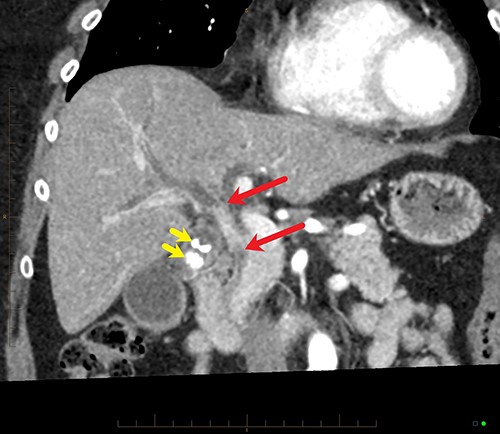

Coronal MPR of late arterial phase CT reveals segmental common hepatic duct stricture with circumferential wall thickening and enhancement (between red arrows) resulting in intrahepatic duct dilatation. Radiopaque calculi (yellow arrows) in the gallbladder.

Final histopathological assessment of the resected specimen reported a common bile duct adenocarcinoma (cholangiocarcinoma) measuring 37Â mm in greatest dimension with extensive perineural, periductal, perinodal and peripancreatic soft tissue involvement. Metastatic carcinoma was found in 3/17 lymph nodes resected. The cholangiocarcinoma was staged as pT2N1M0. The gallbladder was found to have extensive high-grade biliary intraepithelial neoplasia with a primary gallbladder adenocarcinoma measuring 18Â mm in greatest dimension entirely separate from the cholangiocarcinoma (Fig. 5). The patient recovered well from the procedure and was discharged home from hospital on post-operative Day 15. She has proceeded to have further treatment with adjuvant chemotherapy.